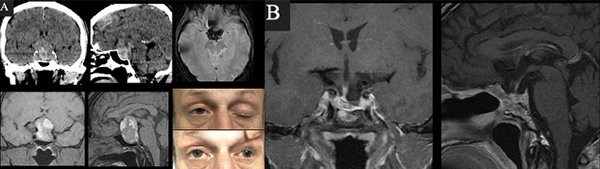

Caso 2. A. Preoperatorio. Varón de 54 años que consultó por cefalea, náuseas y vómitos. Al examen físico presentaba disminución de la AV y III par completo izquierdo +. En la TC y RM de cerebro e hipófisis se evidenciaba una lesión selar-supraselar voluminosa con contenido hemático. B. Postoperatorio. RM que demuestra resección completa de la lesión.

Caso 3. A. Preoperatorio. Paciente de 31 años, anticoagulado por TEP derivado de otro hospital por disminución aguda de la visión. La RM de hipófisis evidenciaba una lesión selar-supraselar voluminosa con un gran contenido hemorrágico. El CVC objetivaba amaurosis derecha y hemianopsia izquierda. B. Postoperatorio. RM que demuestra resección completa de la lesión y CVC con mejoría parcial.